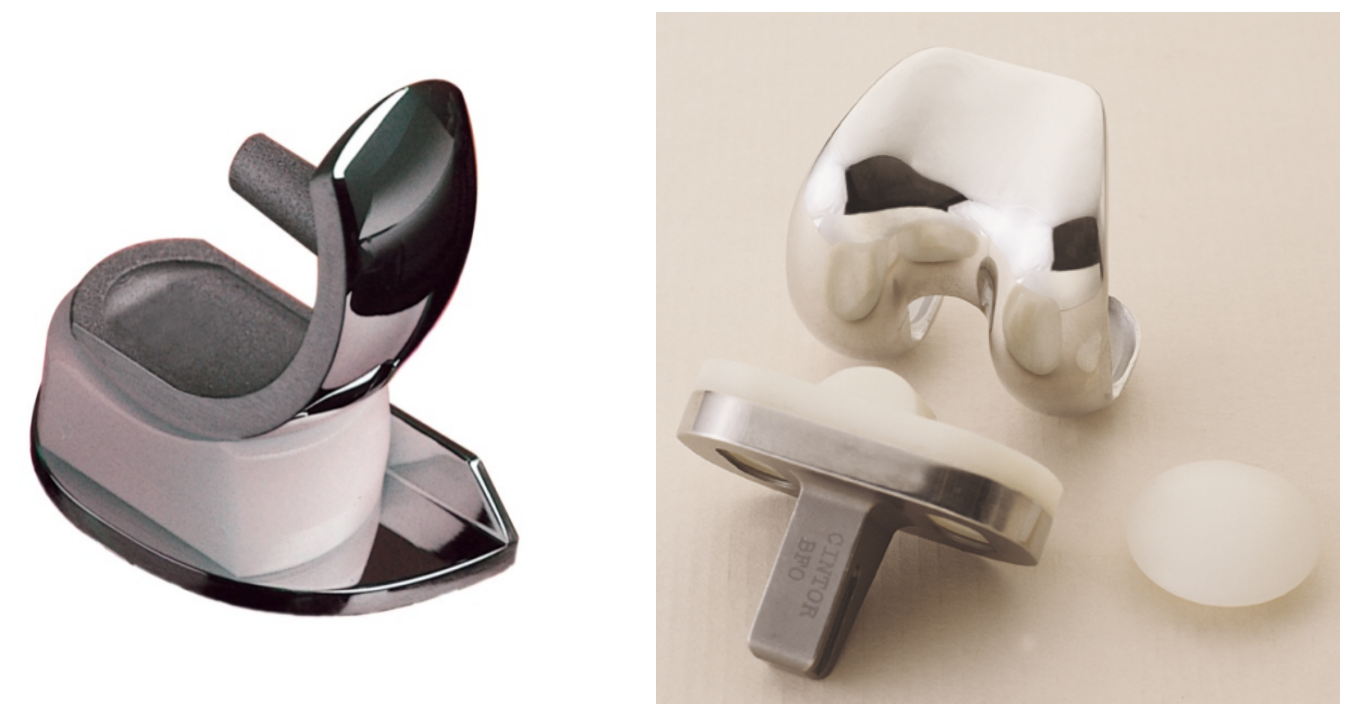

微创膝关节单髁置换假体(左)与全膝关节置换假体(右)

根据解剖特点,膝关节按空间可分为内侧间室、外侧间室、髌股关节间室和髁间窝。膝关节置换手术的范围包括股骨远端和胫骨远端相对应的关节面(双间室置换术),部分还包括髌股关节面(三间室置换术)。但如果患者的膝关节退化仅涉及膝关节内侧单间室,这时候就可以考虑行微创膝关节单髁置换术(单间室置换术)了。但是单间室置换术适应症较局限,手术前必须经过详细的检查才能确定患者是否符合手术指征,而非每个膝关节骨性关节炎的患者都适合手术。下面我们来看一下究竟有哪些条件:

较传统的双间室置换术或三间室置换术,微创膝关节单髁置换术出血量少、恢复迅速、术后本体感觉存在等优点,患者术后满意度高、功能更好,有着更好的治疗体验。